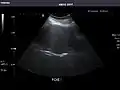

Right kidney